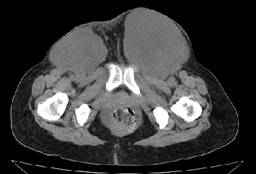

Figura 1: Tomografía computarizada simple de pelvis, cortes a 3 mm con reconstrucción MPR sagital